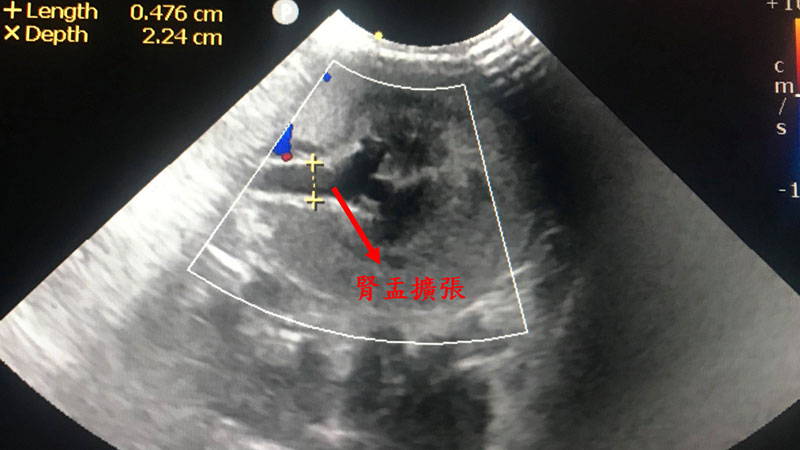

血液抹片呈現不再生性貧血,尿液檢查呈現低比重尿1.007(正常貓咪應在1.030以上),超音波顯示腹腔無明顯出血,但左腎萎縮、右腎輸尿管擴張最終診斷貓咪為急性腎損傷、貧血。